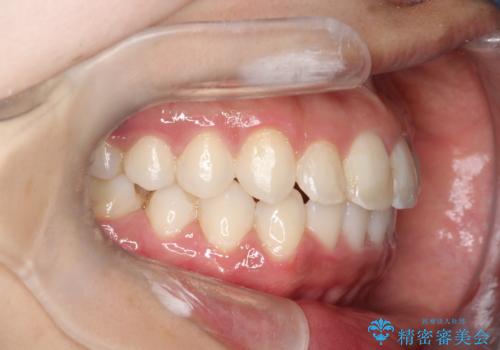

【非抜歯矯正】できる限り前歯を引っ込めたい

- 前歯の凸凹を主訴に来院されました。

非抜歯の範囲でできるだけ前歯を下げることを希望されたため、IPRと臼歯部の遠心移動を行い治療を行いました。当初はインビザラインで治療を行っておりましたが、使用時間を十分に確保できないことで途中からワイヤーを使用しております。